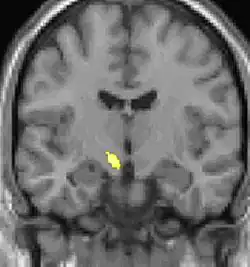

| Diese Kernspintomographie mit eingezeichneter Morphometrie zeigt einen höheren Anteil an Grauer Substanz im Hypothalamus rechts (im Bild links) | ||

Die Positronen-Emissions-Tomographie (PET)-Darstellungen oben zeigen die funktionellen Daten, also die Bereiche, welche bei Schmerzen Aktivität aufweisen, im Vergleich zum Aussehen bei einem schmerzfreien Intervall. Man sieht die sog. Schmerzmatrix, die immer bei Schmerz aktiviert ist und das Areal in der Mitte (in allen drei Ebenen), welches spezifisch im Cluster-Kopfschmerz aktiviert ist. Die VBM Bilder unten zeigen die strukturellen Daten. Hier wird untersucht, ob die Gehirne von Cluster-Kopfschmerz-Patienten anders sind als die Gehirne von Menschen ohne Kopfschmerzen. Nur ein Areal ist anders, da es mehr Graue Substanz enthält: Dieses entspricht dem oben gezeigten funktionellen Areal. Es handelt sich um den Hypothalamus. Dort wird unter anderem der Schlaf-Wach-Rhythmus generiert. Man vermutet daher den Motor des Cluster-Kopfschmerzes im Hypothalamus.[27][28] Mit der 1H-Magnetresonanzspektroskopie konnten auch biochemische Unterschiede zwischen dem Hypothalamus gesunder Menschen und dem Hypothalamus von Cluster-Kopfschmerz-Patienten nachgewiesen werden.[29][30]